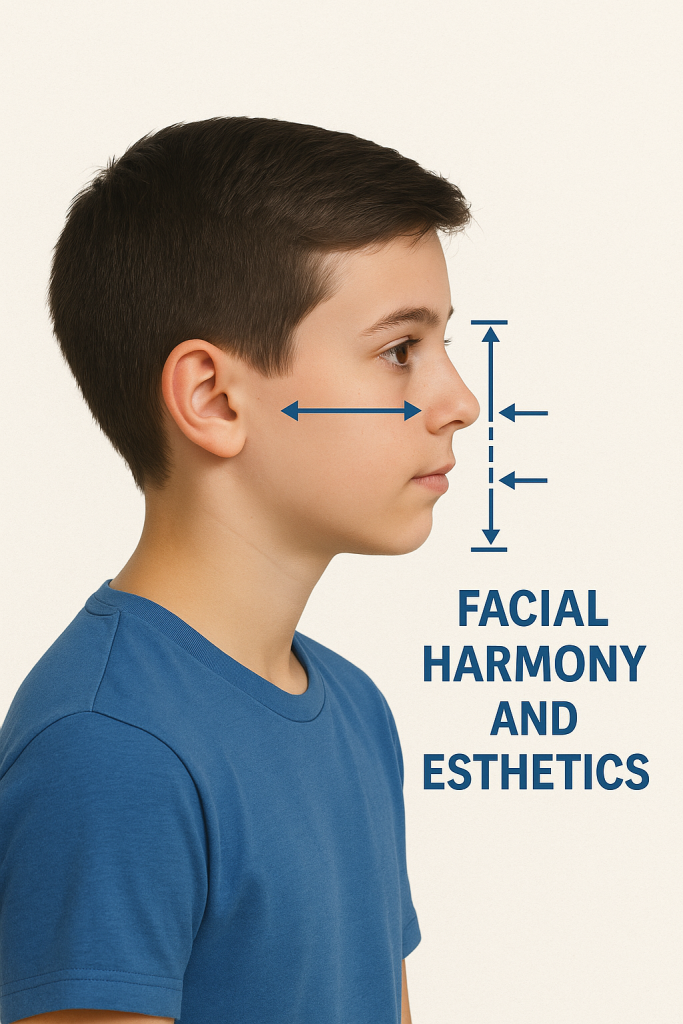

۵. بررسی هماهنگی اجزای صورت و زیبایی چهره

ارتودنسی فقط ردیف کردن دندانها نیست؛

بلکه ایجاد تعادل و زیبایی در کل چهره است.

سفالومتری کمک میکند:

- موقعیت لبها نسبت به بینی و چانه

- زاویه فک پایین

- فاصله لبها از خط زیبایی

- فرم پروفایل صورت (ایدهآل، مقعر، محدب)

بهطور دقیق تحلیل شود.

این موضوع بسیار مهم است زیرا:

در برخی افراد دندانها ظاهراً نامرتباند، اما مشکل اصلی «موقعیت غلط فک» است. اصلاح اشتباه میتواند پروفایل چهره را بدتر کند.

سفالومتری مانع چنین اشتباهی میشود.